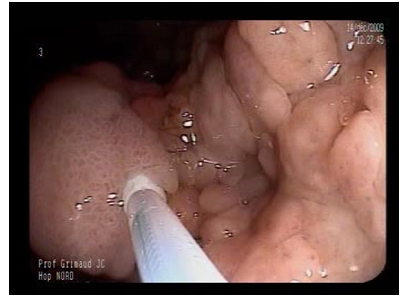

A 62-year-old woman, known to have AFAP, underwent total colectomy with ileo-rectal anastomosis at the age of 45. Surveillance by upper and lower gastrointestinal endoscopy was performed regularly. The last one showed normal rectal and ileal mucosa. Upper gastrointestinal endoscopy was done and revealed normal papilla and duodenal mucosa; however the stomach showed numerous fundic gland polyps, many of them had a large diameter ranging from 1 to 3 cm, along the great curvature (Figure 4a).

Gastric polyps (FGPs and adenomas) before multiple EMR.

Figure 4a: Gastric polyps (FGPs and adenomas) before multiple EMR.

Biopsies confirmed the adeno-villous type of these polyps with low-grade dysplasia. Therapeutic endoscopic procedure was performed for resection of the large polyps (Figure 4b and 4c).

EMR of adenomatous FGP (snare resection)

Figure 4b: EMR of adenomatous FGP (snare resection)

Scar after EMR of adenomatous FGP

Figure 4c: Scar after EMR of adenomatous FGP

Extensive mucosectomy had been successful to resect a large area of gastric fundus affected by large polyps (Figure 4d).

Results after extensive EMR (iscan view; Pentax scope, Japan)

Figure 4d: Results after extensive EMR (iscan view; Pentax scope, Japan)

Pathologic examination confirmed the adenomatous nature of these FGPs, and low and high grade dysplasias were described in many fragments of the mucosectomy.